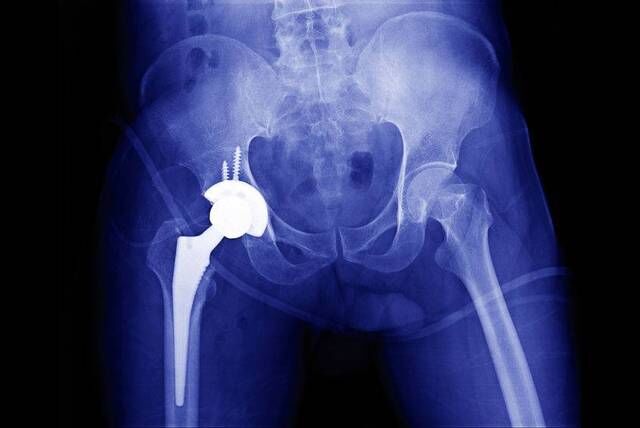

但有一种被称为“人生最后一次骨折”的髋部骨折,一旦遇上了,对于老年人来说,也许就意味着死亡。

根据相关数据统计,发生髋部骨折的老年人之中,死亡率高达50%。然而,国内食道癌一年内的生存率能达到54%,乳腺癌患者的一年生存率甚至能达到95%。

这意味着,髋部骨折的生存率比癌症还低!

所以,髋部骨折才被人们称为“人生最后一次骨折”。